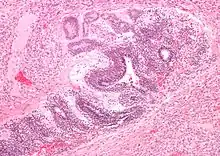

Micrograph of the primitive neuroepithelium of an immature teratoma of the mediastinum. H&E stain.

The mediastinum has three main parts: the anterior mediastinum (front), the middle mediastinum, and the posterior mediastinum (back). Masses in the anterior portion of the mediastinum can include thymoma, lymphoma, pheochromocytoma, germ cell tumors including teratoma, thyroid tissue, and parathyroid lesions. Masses in this area are more likely to be malignant than those in other compartments.[2][3]